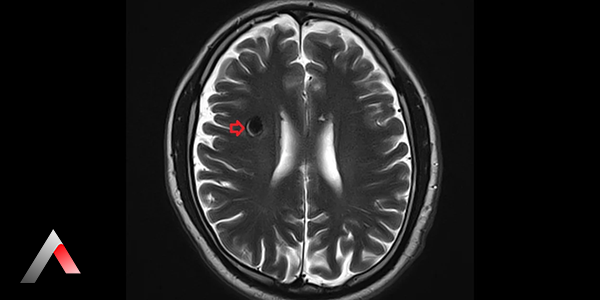

Kavernom, beyinde veya omurilikte oluşan, anormal şekilde gelişmiş kan damarlarının bir araya gelerek oluşturduğu bir kütledir. Kavernöz malformasyon, kavernöz anjiyom veya serebral kavernom olarak da adlandırılan bu oluşumlar, genellikle doğuştan gelir ve çoğu zaman belirti vermezler. Ancak, nadir durumlarda kanama, nöbet veya diğer nörolojik problemlere yol açabilirler.

Kavernom, beyinde veya omurilikte oluşan, anormal şekilde gelişmiş kan damarlarının bir araya gelerek oluşturduğu bir kütledir. Bu damarlar, normal kan damarları gibi düzgün bir yapıya sahip değildir ve ince duvarlı, genişlemiş ve düzensiz şekillidir. Kavernomlar, genellikle küçük boyutludur (birkaç milimetre ile birkaç santimetre arasında) ve tek başına veya birden fazla sayıda olabilirler. Çoğu zaman doğuştan gelir, yani kişi doğduğunda mevcuttur. Ancak, bazı durumlarda sonradan da gelişebilirler. Kavernomların neden oluştuğu tam olarak bilinmemektedir, ancak genetik faktörlerin rol oynadığı düşünülmektedir.

• Manyetik rezonans görüntüleme (MR): Beynin detaylı görüntülerini elde etmek için kullanılan bir görüntüleme yöntemidir. MR, kavernomları teşhis etmek için en etkili yöntemdir.